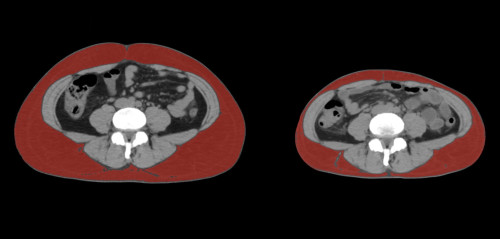

②

40代・女性(ご本人のご厚意で画像提供)

治療内容:チルゼパチド2.5mgの週1回自己注射による脂肪減少と脂肪肝改善

治療期間: 6ヶ月(26週)((用量は2.5mgから開始し最大で15mg。減量効果が得られる必要用量には個人差があります。))

費用:自由診療の場合は4400円(税込)×26(週)=114400円

想定されるリスク・副作用:下記に副作用を記載

※医療広告ガイドラインに準拠して表記

1:脂肪の減少

皮下脂肪の減少(赤色部分)